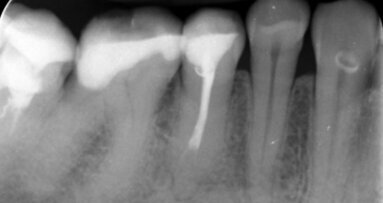

Przedstawiono obraz kliniczny wyjściowy 47-letniej pacjentki ze zdiagnozowaną zaawansowaną uogólnioną chorobą przyzębia, licznymi brakami zębowymi, brakiem protetycznego uzupełnienia zębów bocznych, zmianami okołowierzchołkowymi, niepełnym leczeniem endodontycznym. Pacjentka wymagająca kompleksowego leczenia stomatologicznego. Aby stworzyć wyjściowy plan leczenia, konieczne jest wdrożenie leczenia wstępnego (faza higienizacyjna), aby sprawdzić motywację pacjentki do dalszego leczenia wysokospecjalistycznego i ocenić rokowanie zębów.

Po higienizacji stan kliniczny pacjentki poprawił się. Wykonano kontrolne badania obrazujące zaawansowanie choroby przyzębia.

Następnie zastosowano laser Nd:YAG do sterylizacji kieszeni przyzębnych, dekontaminacji (Ryc. 3-7) i laser Er:YAG do usunięcia kamienia poddziąsłowego (Ryc. 8-12) oraz ponownie laser Nd:YAG do stabilizacji skrzepu (Ryc. 13 i 14). Na rycinie 15 przedstawiono stan bezpośrednio po zabiegu usunięcia kamienia poddziąsłowego laserem Er:YAG wraz ze sterylizacją kieszeni przyzębnych laserem Nd:YAG (LightWalker, Fotona).